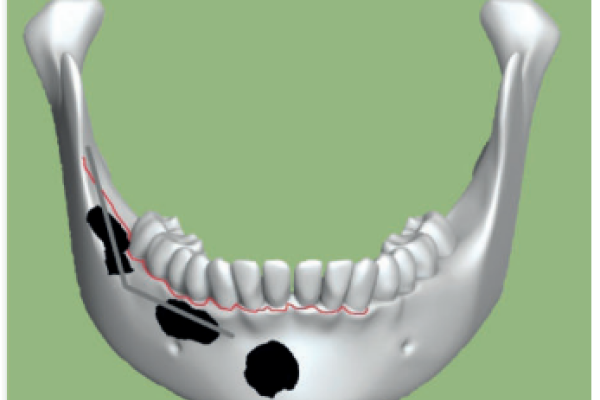

Abordaje mediante tres cavidades de un quiste dentígero de gran tamaño: a propósito de un caso